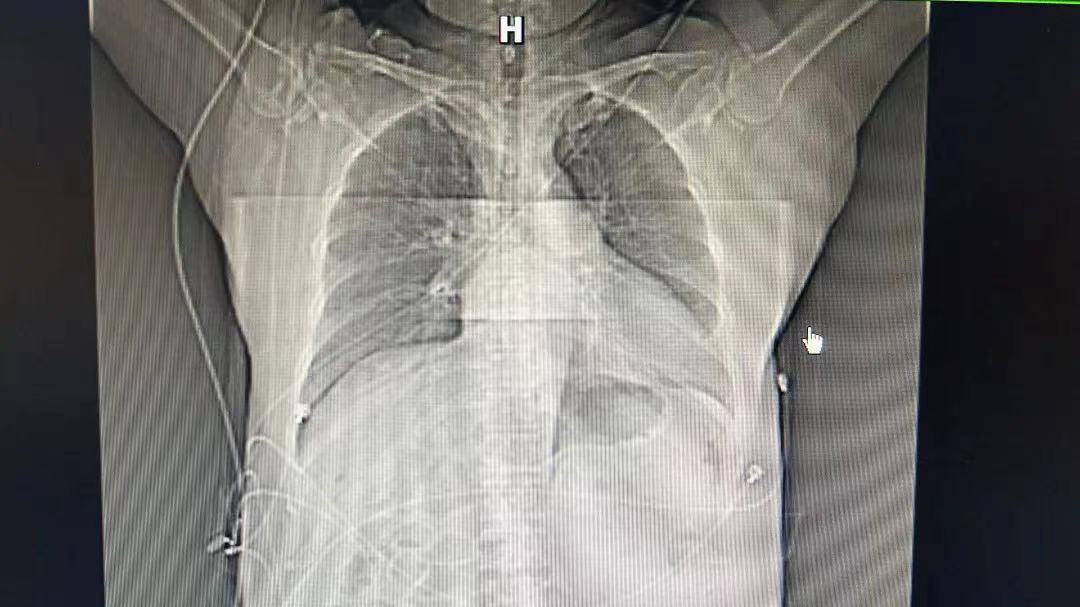

老黄心脏收缩力只有正常人的1/3

心外科主任单忠贵团队发现老黄左心室功能严重降低,仅靠药物无法延缓患者的心衰进程,老黄心力可能随时出现衰竭。